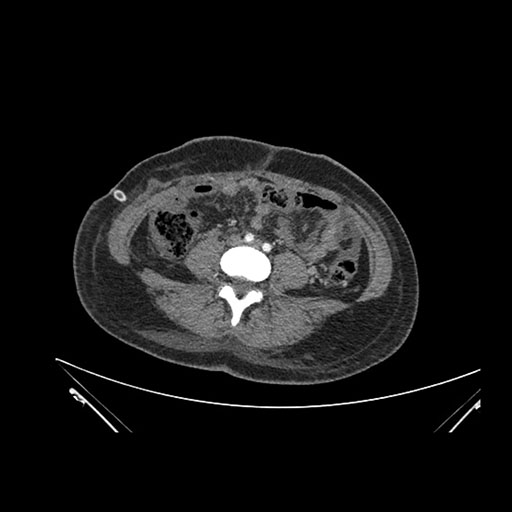

Coronal Venous

Imaging analysis

Based on initial findings, which issue(s) would you be most concerned about?